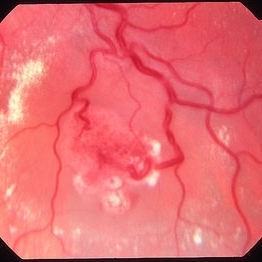

Retinal capillary hemangioma 4 image 2

Jan 11 2013 by Alex P. Hunyor, MD

Retinal capillary haemangioma, left eye, in a young female with von Hippel-Lindau disease. Color image 2 showing the haemangioma with surrounding exudative detachment and lipid exudate.

Condition/keywords: retinal capillary hemangioma, Von Hippel-Lindau